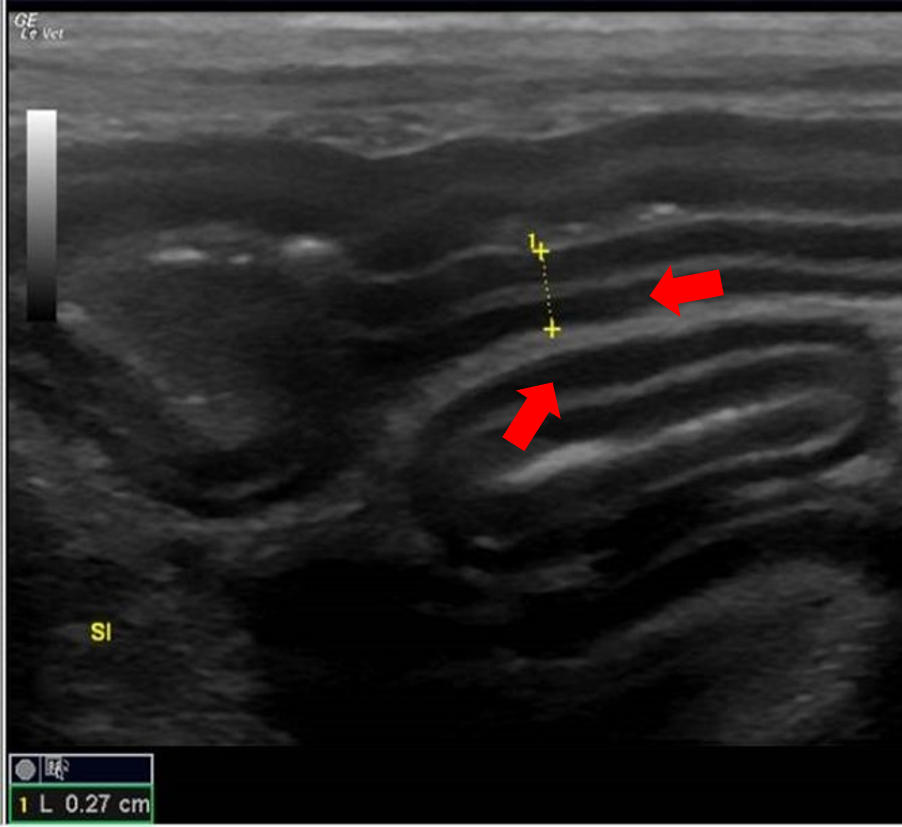

- Total wall thickness or changes in relative wall layer thickness (Figure 8, 9)

Figure 8. Muscularis Layer Thickening – In this image of a cat, sections of jejunum can be seen. Although not thickened overall (one wall thickness is being measured by the yellow callipers – 0.27cm), there is a relative increase in the thickness of the hypoechoic muscularis layer. This change is associated with lymphoma and inflammatory bowel disease in cats. 8